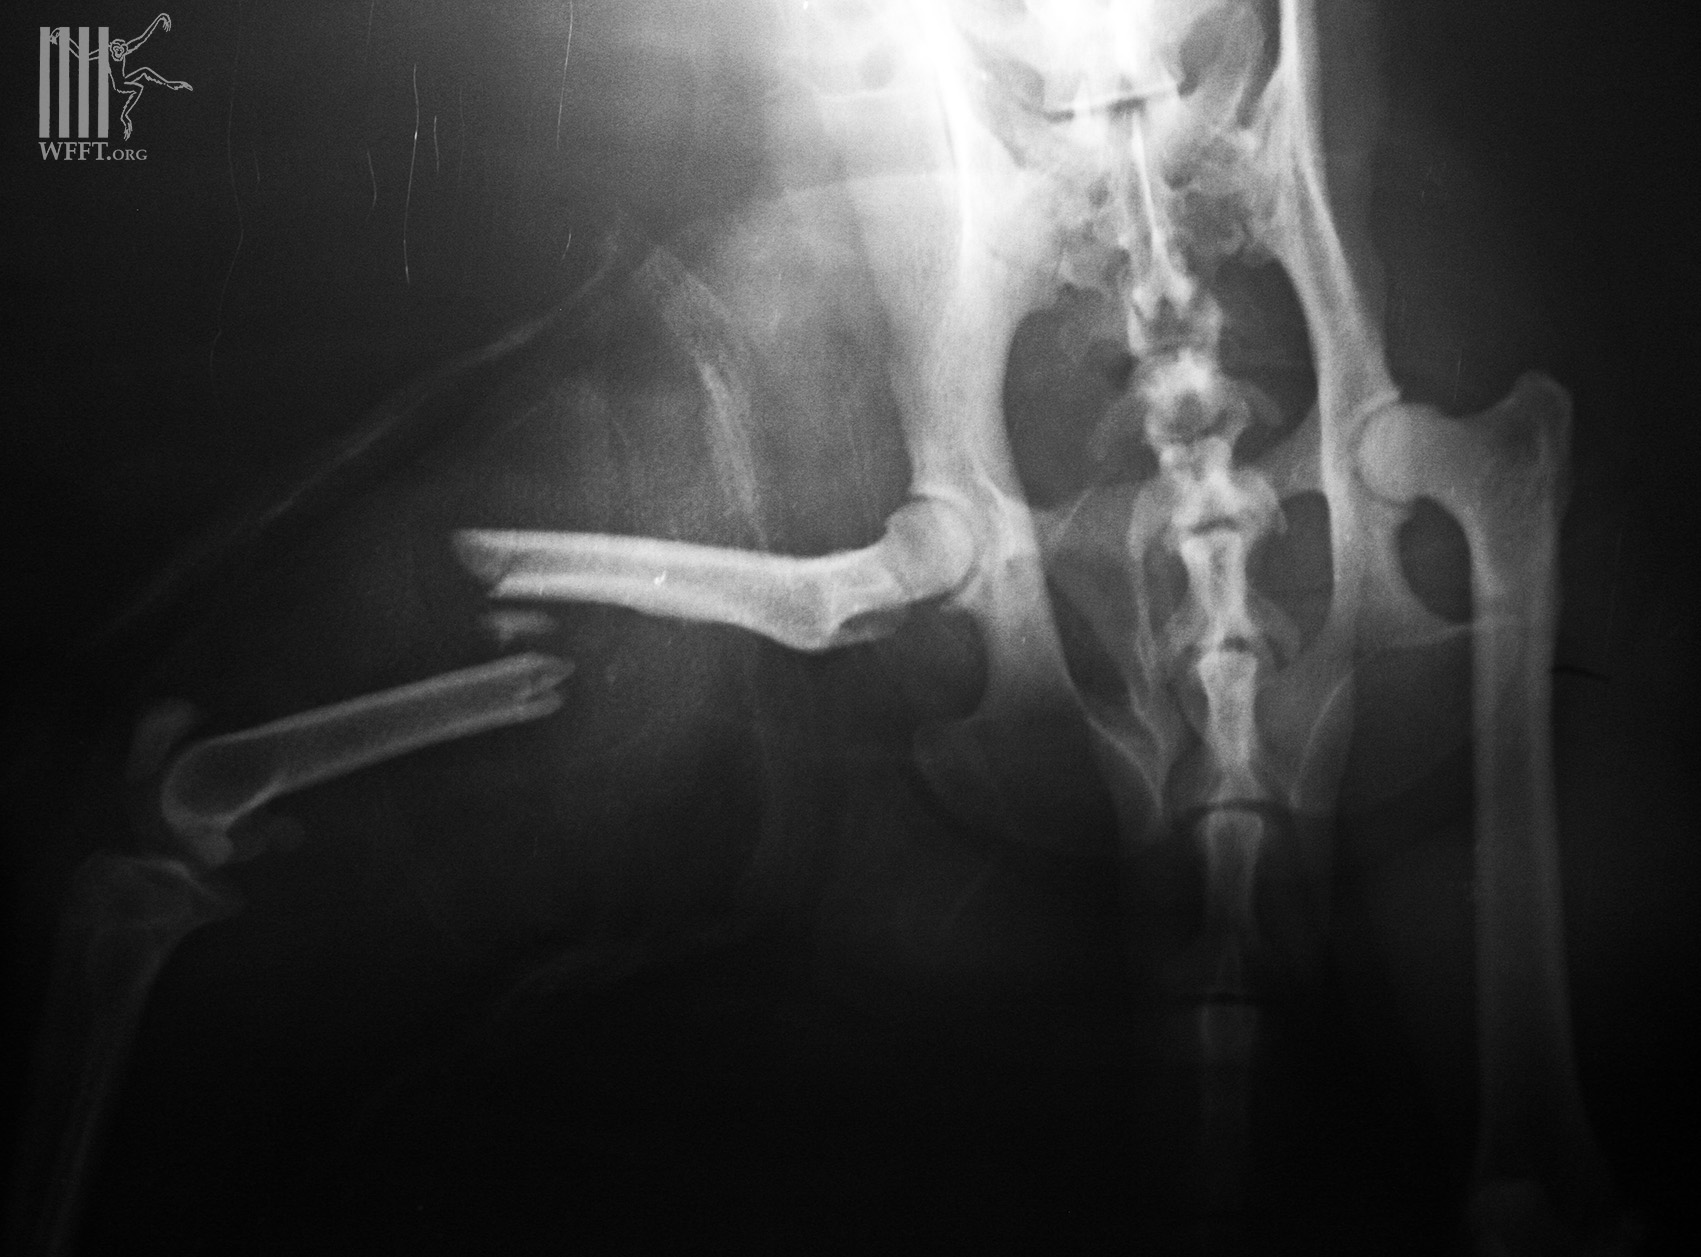

Monkey’s broken leg healing well

Two week slater we are seeing Mr Faifa getting stronger and we are getting ready to let him go back home, to the wild. We hope he remembers to stay away from the power-lines from now on.